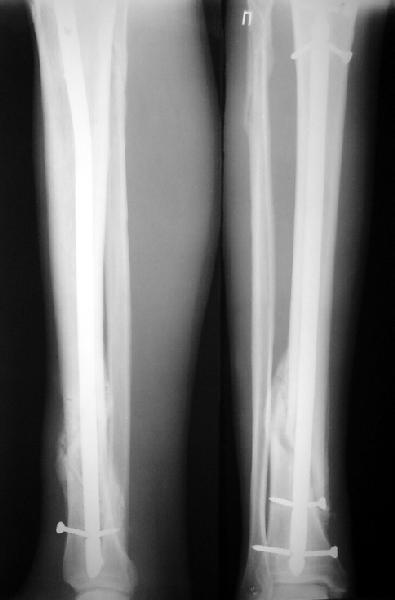

На мой взгляд, на снимках, приведённых Вами - неправильно сростающийся перелом дистальной трети большеберцовой кости, состояние после остеосинтеза интрамедуллярным гвоздём.

Как Вы пишите снимок под номером 1 - менсяц после операции, под номером 2- два месяца после операции.

Вы не послали послеоперационный снимок, поэтому трудно судить о состоянии редукции после операции.

Установка с медиальной стороны гвоздя в области дистального фрагмента дополнительного шурупа помогло бы Вам репонировать и удержать перелом в анатомическом положении, предотвратило варусную деформацию и смещение по ширине.

На мой взгляд внутрикостная фиксация переломов дистальной и проксимальной трети большеберцовой кости, за исключением поперечных, не очень хорошее решение вопроса, аппарат Илизарова или Тэйлора, позволяющие призвести закрытую анатомическую редукцию и отличное удержание отломков в период сращения.

Пример, приведённый Вами в нашей дискуссии по времени нагрузки после остеосинтеза не совсем удачный... Ваш больной имеет счастье, что первым согнулся проксимальный замыкающий винт, а не дистальный и гвоздь не пенетрировал голеностопный сустав.